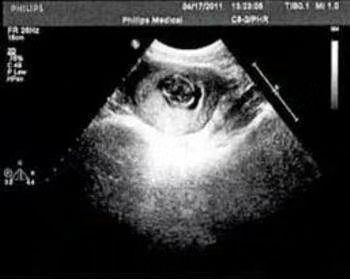

贺峻霖

宋亚轩这是!

宋亚轩恭喜你啊贺儿!